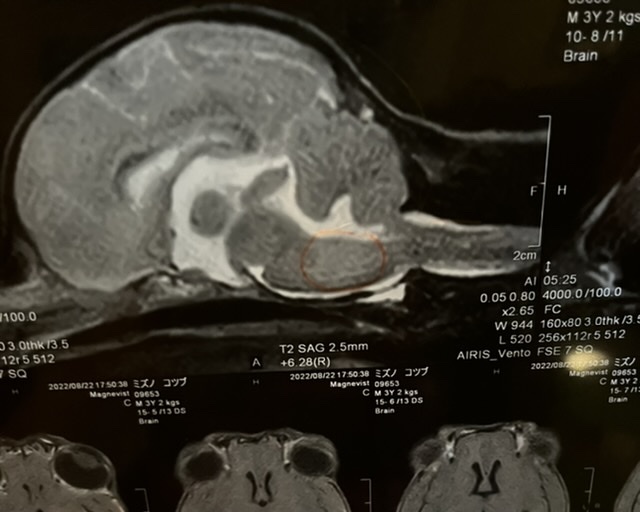

2022年8月22日

MRI検査の結果、脳脊髄炎と診断されました。

同時に脳脊髄液検査をする予定でしたが、脳の腫れがひどく、採取することで脳がずれてしまい亡くなる可能性があるとの事で今回は採取はできませんでした。

脳脊髄液検査をする事で、感染性か非感染性なのかが判明するようですが、こつぶの場合、若くて発症しているので、非感染性で原因不明自己免疫の異常ではないかと言われました。

すぐに治療を開始しないと1ヶ月もつかどうかと言われ、入院し抗がん剤治療を2日間することになりました。

*病院より掲載のお許しは頂いております